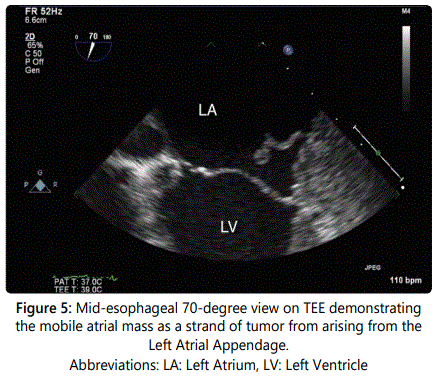

A 54-year-old gentleman with recently diagnosed Stage IIIB squamous cell carcinoma of the lung with metastases to the lymph nodes had a transthoracic echocardiograph (TTE) performed for evaluation of progressive dyspnea on exertion. A large pericardial effusion causing tamponade physiology was noted on TTE and the Computerized Tomography (CT) image of the thorax (Figures 1 and 2). Following a pericardi ocentesis, a repeat TTE was performed which showed the presence of a left atrial mass (Figure 3). The mass was initially reported as a 1.3x0.5 cm pedunculated mobile left atrial mass arising from the left atrial appendage prolapsing in the mitral orifice in diastole before further assessment with a transesophageal echocardiogram (TEE) was performed. The TEE demonstrateddirect invasion of the mass from the left upper pulmonary vein into the left atrial appendage with minimal residual flow of that pulmonary vein and complete opacification of the left atrial appendage as well as invasion of the superior vena cava (Figure 4). The mobile mass in the left atrium was a strand of tumor that extended from the edge of the left atrial appendage (Figures 5 and 6).

Metastases to heart are significantly more common than primary cardiac tumors with an approximate 20-40x the prevalence of that of primary tumors [1,2]. While historically a post-mortem finding, cardiac metastases are becoming increasingly diagnosed in living individuals with advances in imaging modalities including echocardiography (TTE and TEE), CT, MRI, and Positron Emission Tomography [3,4]. Here, we describe a rare example of direct invasion from squamous cell carcinoma of the lung of a mobile mass in the left atrium on TTE that was better visualized with TEE.